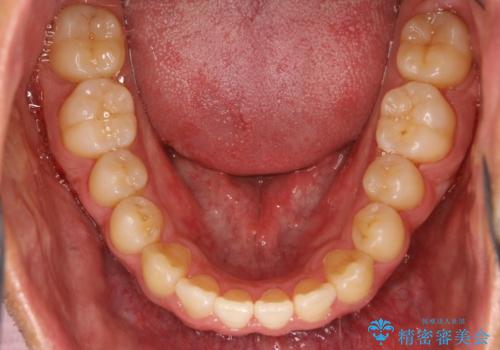

前歯が反対にかんでいる インビザラインとワイヤーを組み合わせた矯正治療

- 前歯が正常とは反対にかんでいるとのことで、来院されました。

マウスピースのみでの治療も可能でしたが、治療期間がもう少し延長していた可能性があります。

器具や治療方法についても、矯正治療の前にしっかり相談させていただきます。